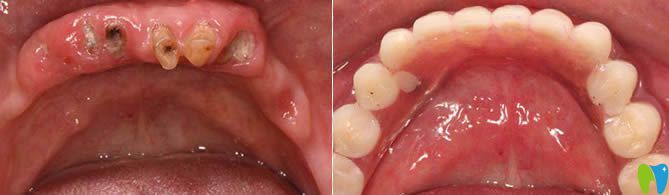

1、60歲老人全口種植牙前后對(duì)比及顧客反饋:

西安諾貝爾口腔李江院長(zhǎng)60歲老人全口種植牙前后對(duì)比<span style=

【顧客評(píng)價(jià)】:這家在我們當(dāng)?shù)厥莻€(gè)老品牌,很早都聽說比較出名,這次種牙也是我個(gè)咨詢的牙科。很正規(guī),環(huán)境也很舒適,我是早上檢查完,下午就完成了全口種植牙,感覺諾貝爾的種牙技術(shù)很靠譜,給醫(yī)生們點(diǎn)贊。